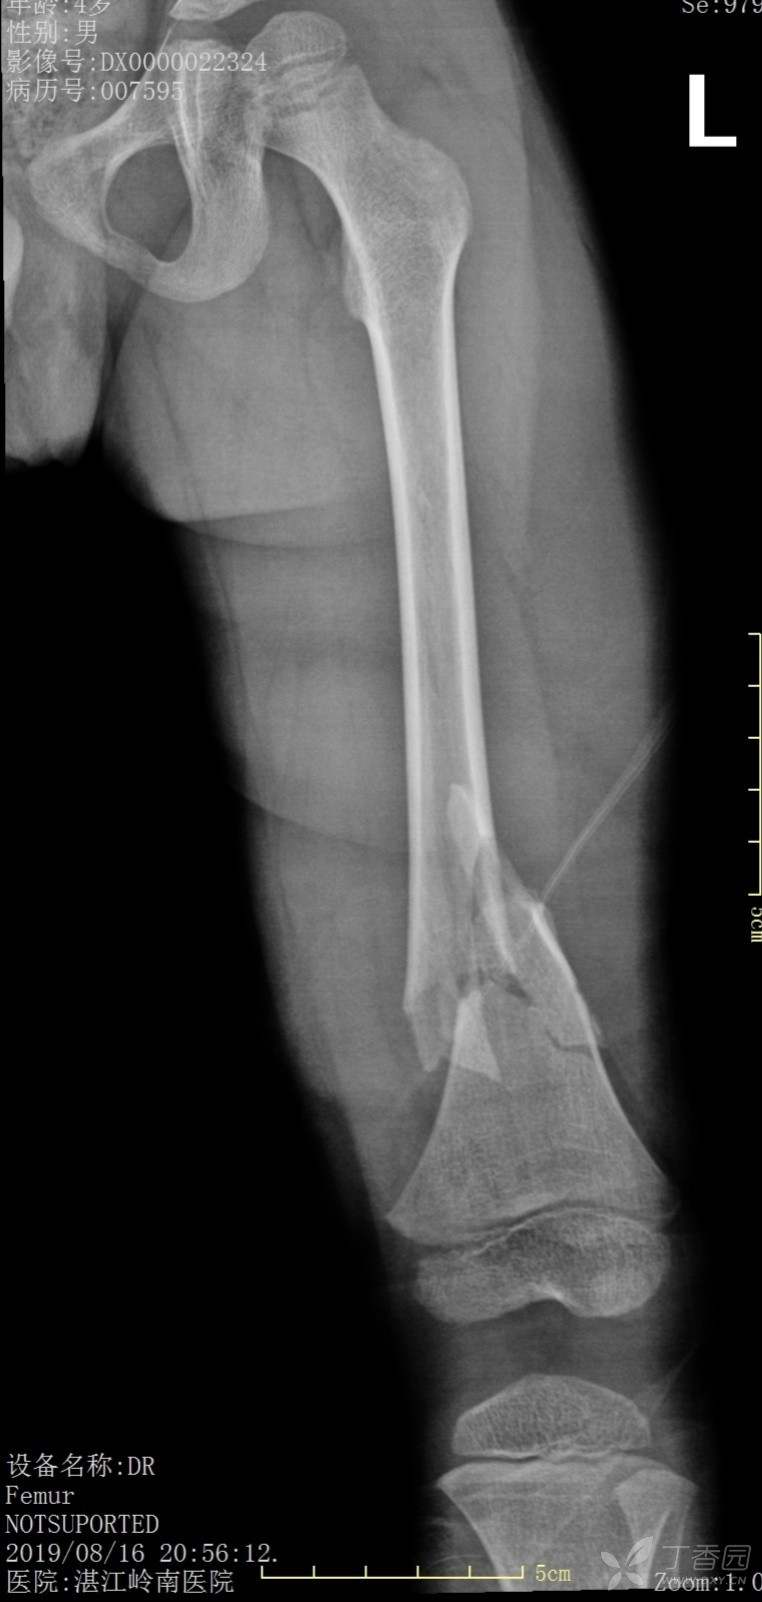

4岁患儿股骨骨折保守治疗一例

外伤时,保守1个月、2个月、6个月